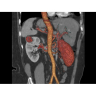

Кардиология

• Неинвазивная оценка состояния коронарных артерий.

• Диагностика атеросклероза и других сердечно-сосудистых патологий.